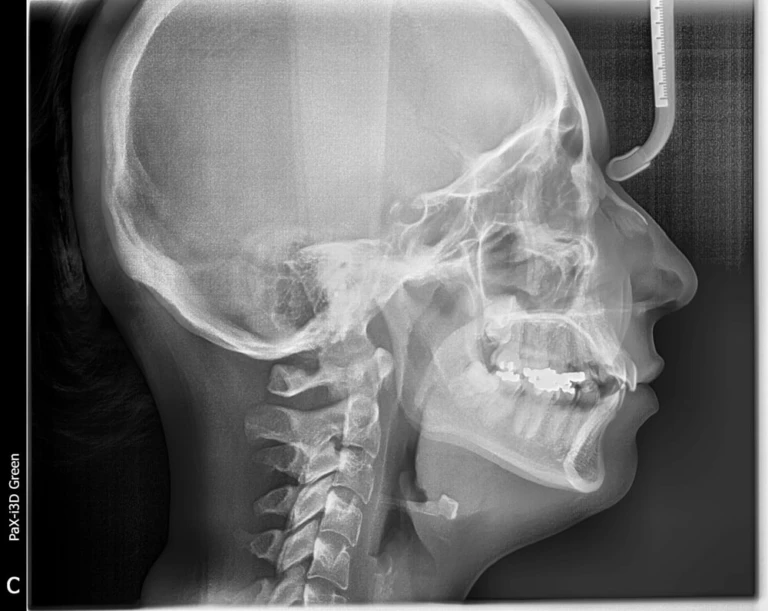

Đọc tiếpA- GIỚI THIỆU Phim Cephalometric là một phương pháp tiêu chuẩn để tái tạo lại hình ảnh sọ mặt, rất…